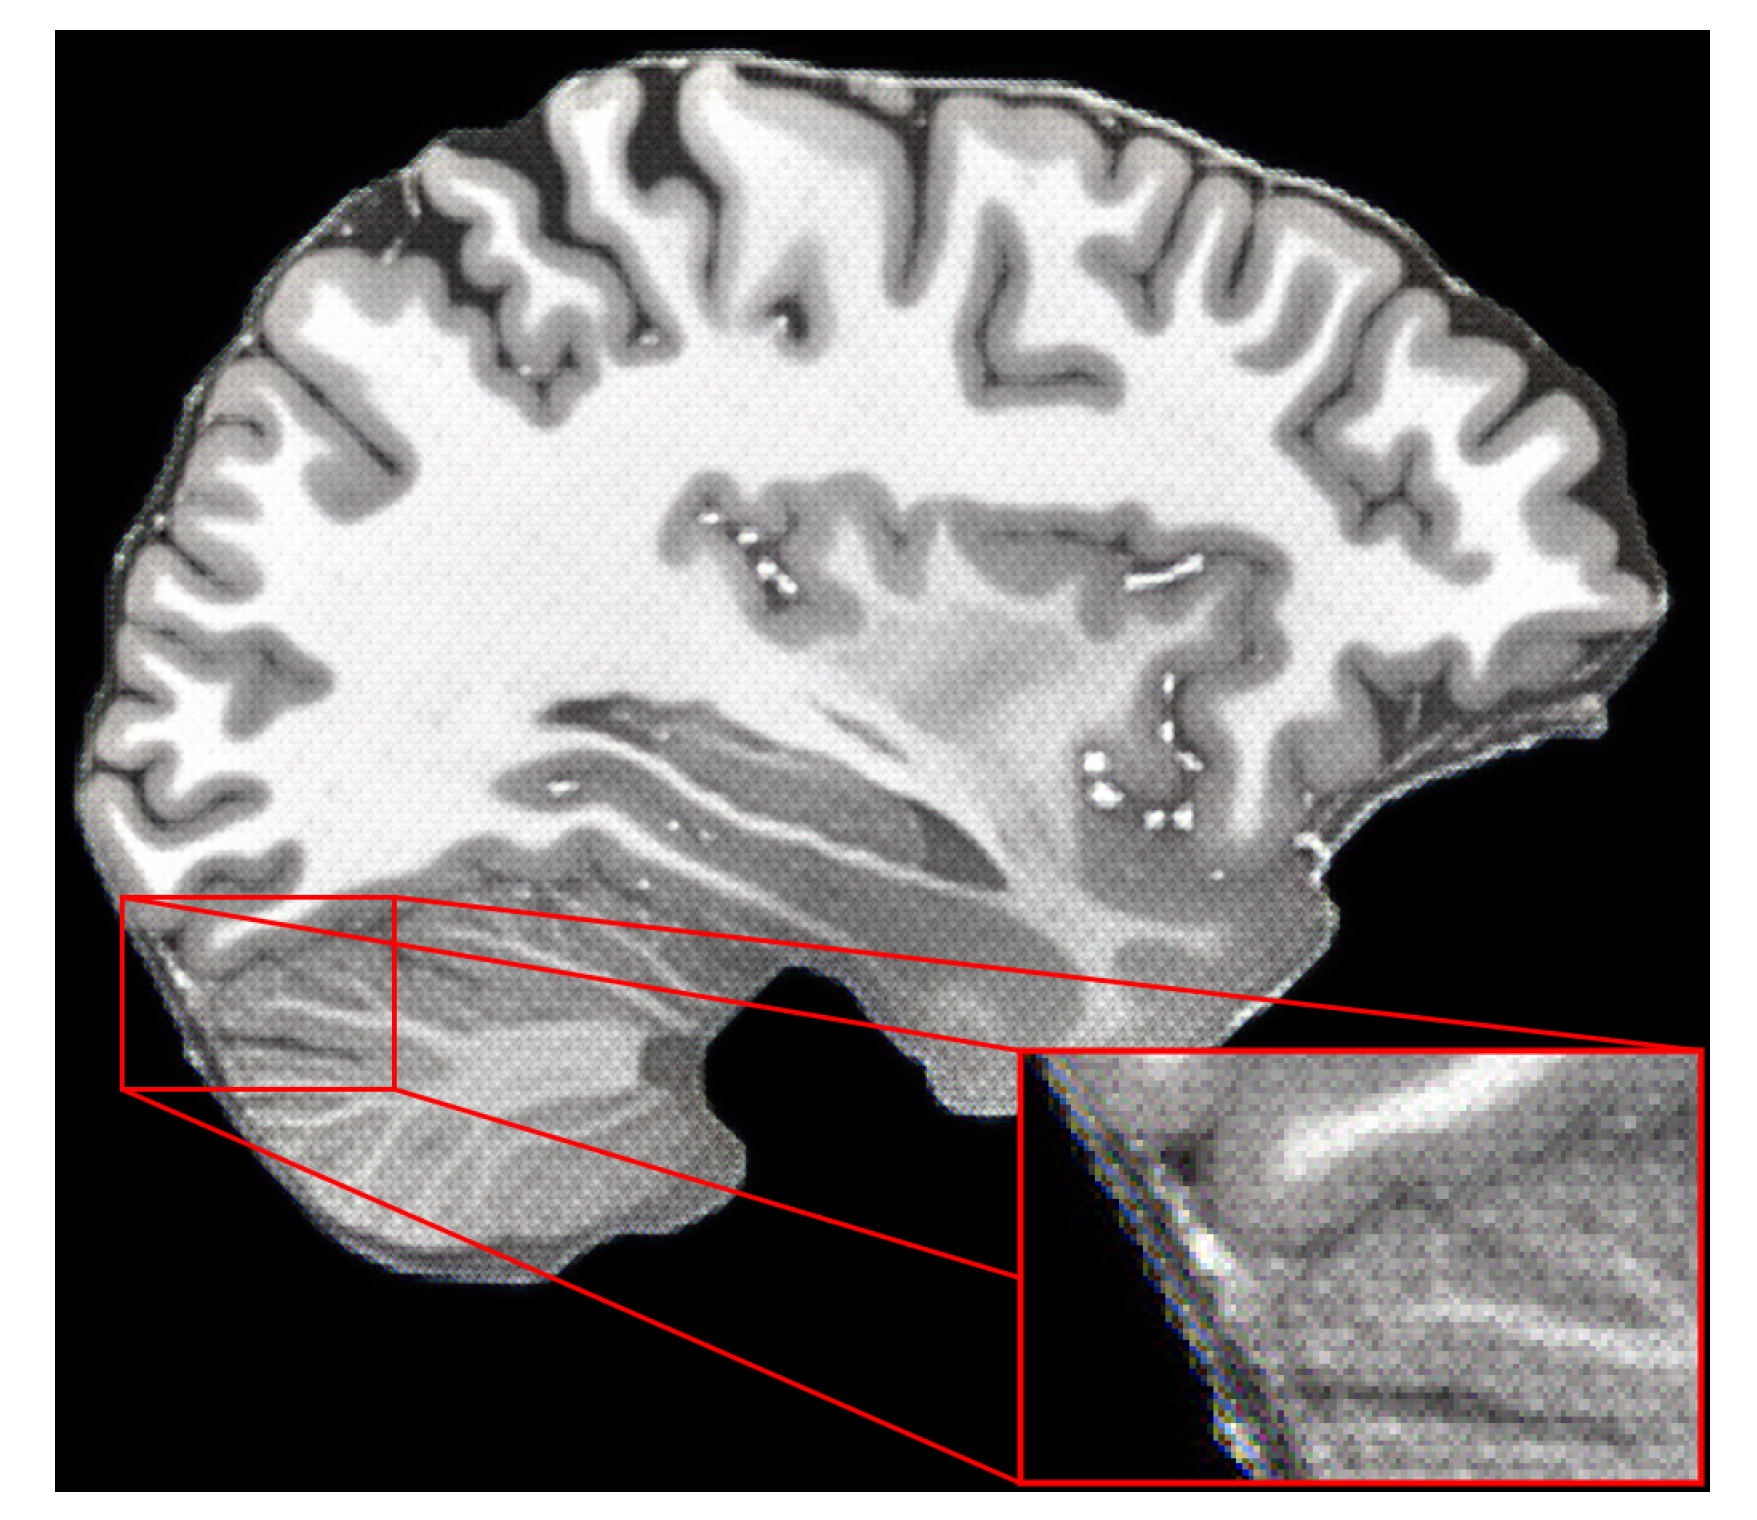

- Lusebrink, F.; Mattern, H.; Yakupov, R.; Acosta-Cabronero, J.; Ashtarayeh, M.; Oeltze-Jafra, S.; Speck, O. Comprehensive Ultrahigh Resolution Whole Brain In Vivo MRI Dataset as a Human Phantom. Sci. Data 2020, 8, 138. [Google Scholar] [CrossRef]

- Schreiber, S.; Bernal, J.; Arndt, P.; Schreiber, F.; Müller, P.; Morton, L.; Braun-Dullaeus, R.C.; Valdés-Hernández, M.D.C.; Duarte, R.; Wardlaw, J.M.; et al. Brain Vascular Health in ALS Is Mediated through Motor Cortex Microvascular Integrity. Cells 2023, 12, 957. [Google Scholar] [CrossRef] [PubMed]

- Betts, M.J.; Perosa, V.; Hämmerer, D.; Düzel, E. Healthy aging and Alzheimer’s disease. In Advances in Magnetic Resonance Technology and Applications; Elsevier: Amsterdam, The Netherlands, 2023; pp. 537–547. [Google Scholar] [CrossRef]

- Naji, N.; Wilman, A. Thin slab quantitative susceptibility mapping. Magn. Reson. Med. 2023. [Google Scholar] [CrossRef]

- Ladd, M.E.; Quick, H.H.; Speck, O.; Bock, M.; Doerfler, A.; Forsting, M.; Hennig, J.; Ittermann, B.; Möller, H.E.; Nagel, A.M.; et al. Germany’s journey toward 14 Tesla human magnetic resonance. Magn. Reson. Mater. Physics Biol. Med. 2023, 36, 191–210. [Google Scholar] [CrossRef] [PubMed]

- Mattern, H.; Lüsebrink, F.; Speck, O. High-resolution structural brain imaging. In Advances in Magnetic Resonance Technology and Applications; Elsevier: Amsterdam, The Netherlands, 2022; pp. 433–448. [Google Scholar] [CrossRef]